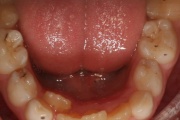

Normaalse jäävhammaskonna pilt küljelt ja eest vaadatuna.